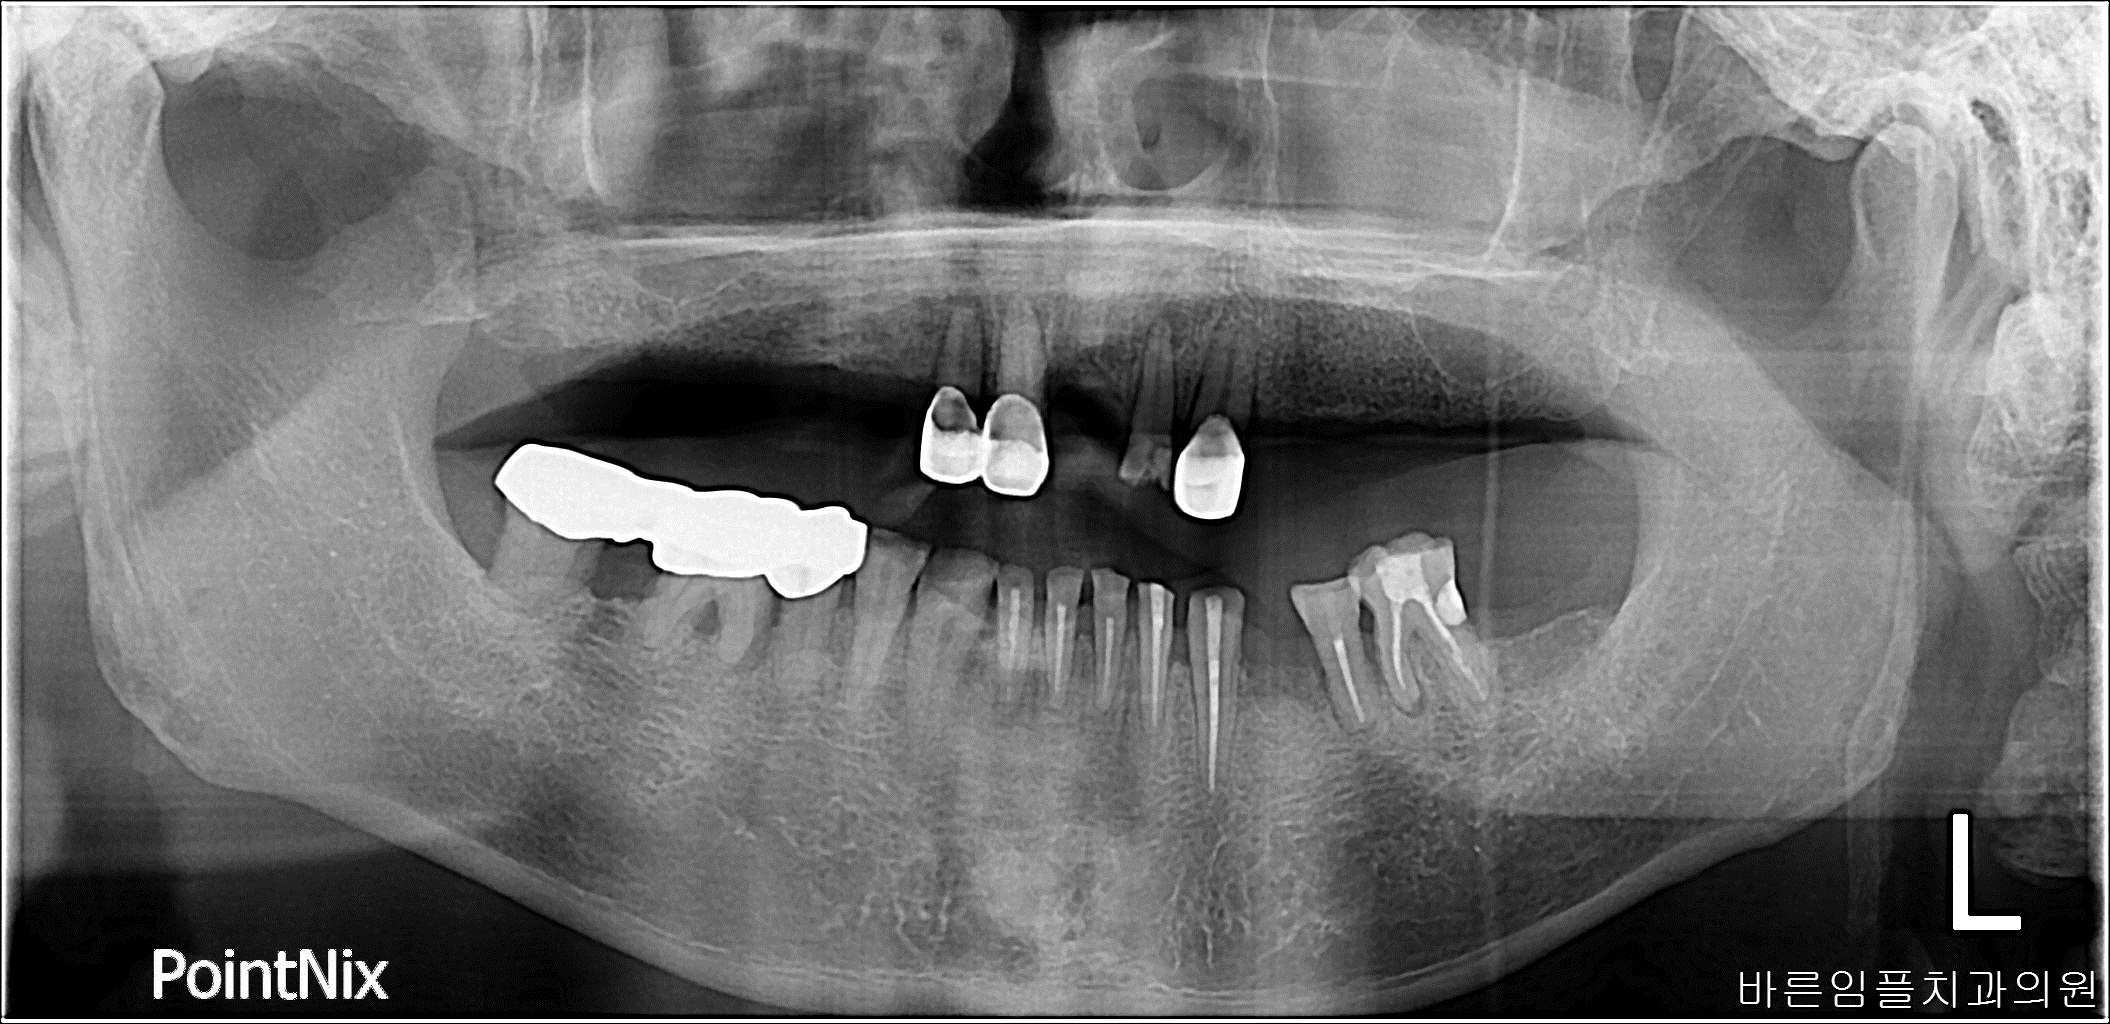

김ㅇㅇ / 임플란트 페이지 정보 작성일 23-10-27 16:55 2023-04-23 김ㅇㅇ Before 2023-08-21 김ㅇㅇ After 김ㅇㅇ / 임플란트 목록 이전글김ㅇㅇ / 수면임플란트